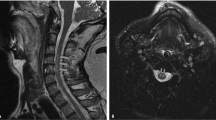

We report a case of a middle-aged man who suffered a cerebral infarction resulting from dissection of a vertebral artery associated with morning blood pressure surge. A 56-year-old man was transferred to our hospital with dizziness and vomiting in the early morning on a cold day in winter. He reported that he had been standing in front of the sink after bathing when he suddenly felt dizzy and fell down. He did not lose consciousness, and by the time he reached the hospital by ambulance, his dizziness had subsided, but he complained of severe headache and vomited 3 times. On admission, he was alert, and there were no neurological or radiological abnormalities (CT, MR angiography) in the brain. However, infarction in the left cerebellar hemisphere was detected by brain MRI on the 5th day of hospitalization. String sign of the left vertebral artery was noted by angiography, confirming the diagnosis of dissection of the left vertebral artery. Ambulatory blood pressure monitoring was performed after discharge. Although the mean 24-h blood pressure was in the normal range, a marked morning blood pressure rise was observed. We speculated that the acute rise of blood pressure in the early morning might have contributed to the dissection of the vertebral artery.